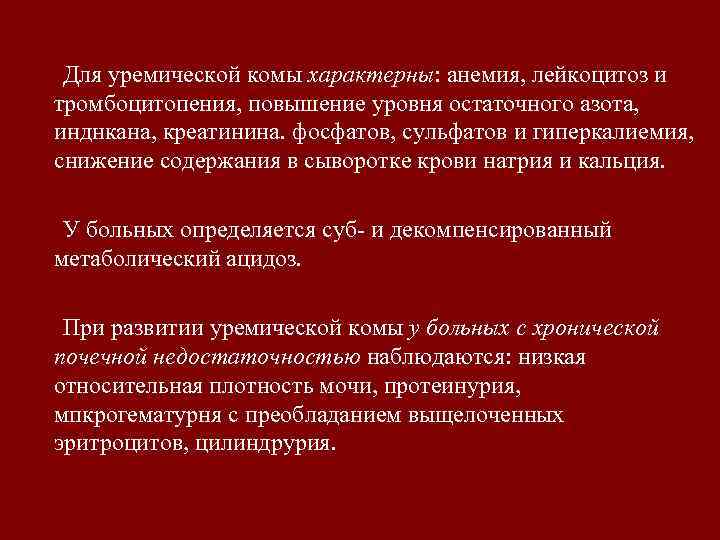

Для уремической комы характерны: анемия, лейкоцитоз и тромбоцитопения, повышение уровня остаточного азота, инднкана, креатинина. фосфатов, сульфатов и гиперкалиемия, снижение содержания в сыворотке крови натрия и кальция. У больных определяется суб- и декомпенсированный метаболический ацидоз. При развитии уремической комы у больных с хронической почечной недостаточностью наблюдаются: низкая относительная плотность мочи, протеинурия, мпкрогематурня с преобладанием выщелоченных эритроцитов, цилиндрурия.

Для уремической комы характерны: анемия, лейкоцитоз и тромбоцитопения, повышение уровня остаточного азота, инднкана, креатинина. фосфатов, сульфатов и гиперкалиемия, снижение содержания в сыворотке крови натрия и кальция. У больных определяется суб- и декомпенсированный метаболический ацидоз. При развитии уремической комы у больных с хронической почечной недостаточностью наблюдаются: низкая относительная плотность мочи, протеинурия, мпкрогематурня с преобладанием выщелоченных эритроцитов, цилиндрурия.